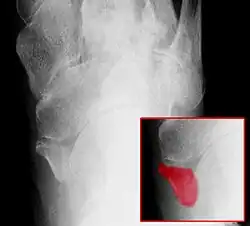

Beim Os tibiale externum (synonym: Os naviculare externum, Os naviculare secundarium, Os naviculare accessorium, Os naviculare bipartitum; englisch accessory tarsal navicular, accessory tarsal scaphoid) handelt es sich um eine häufige (10–16 %) Variation am Kahnbein des Fußes (Os naviculare). In über der Hälfte der Fälle tritt es beidseitig auf.

Es ist eine harte Auftreibung im Sinne eines Überbeins an der inneren Fußwurzel, etwa einen Fingerbreit unter und vor der Innenknöchelspitze, also am Kahnbein, tastbar. Gelegentlich tritt ein Belastungs- und Druckschmerz auf, insbesondere, wenn diese Fehlbildung zusammen mit einem Plattfuß auftritt. Die Diagnose wird mit einem Röntgenbild gesichert.

Es sind drei Formen des Os tibiale externum zu differenzieren:

- Typ 1: Das Os tibiale externum im engeren Sinne ist ein 2–3 mm großes, rundliches Sesambein im Ansatzbereich der Sehne des Musculus tibialis posterior. Es bildet keinen Knorpel zum Kahnbein.

- Typ 2: Das Os tibiale externum ist dreieckförmig und bis zu 9 mm groß. Dieses hat eine Knorpelverbindung zum Kahnbein. Dieser Typ ist mit über 50 % der häufigste. Es handelt sich um eine unterbliebene Verschmelzung der Knochenkerne, aus denen sich das Kahnbein in der frühen Jugend bildet.

- Typ 3: Hier ist das Kahnbein anlagemäßig weit ausladend nach innen ausgebildet (Os naviculare cornutum, englisch cornuate navicular). Hier ist im Gegensatz zu den ersten beiden Formen kein Spalt auszumachen.